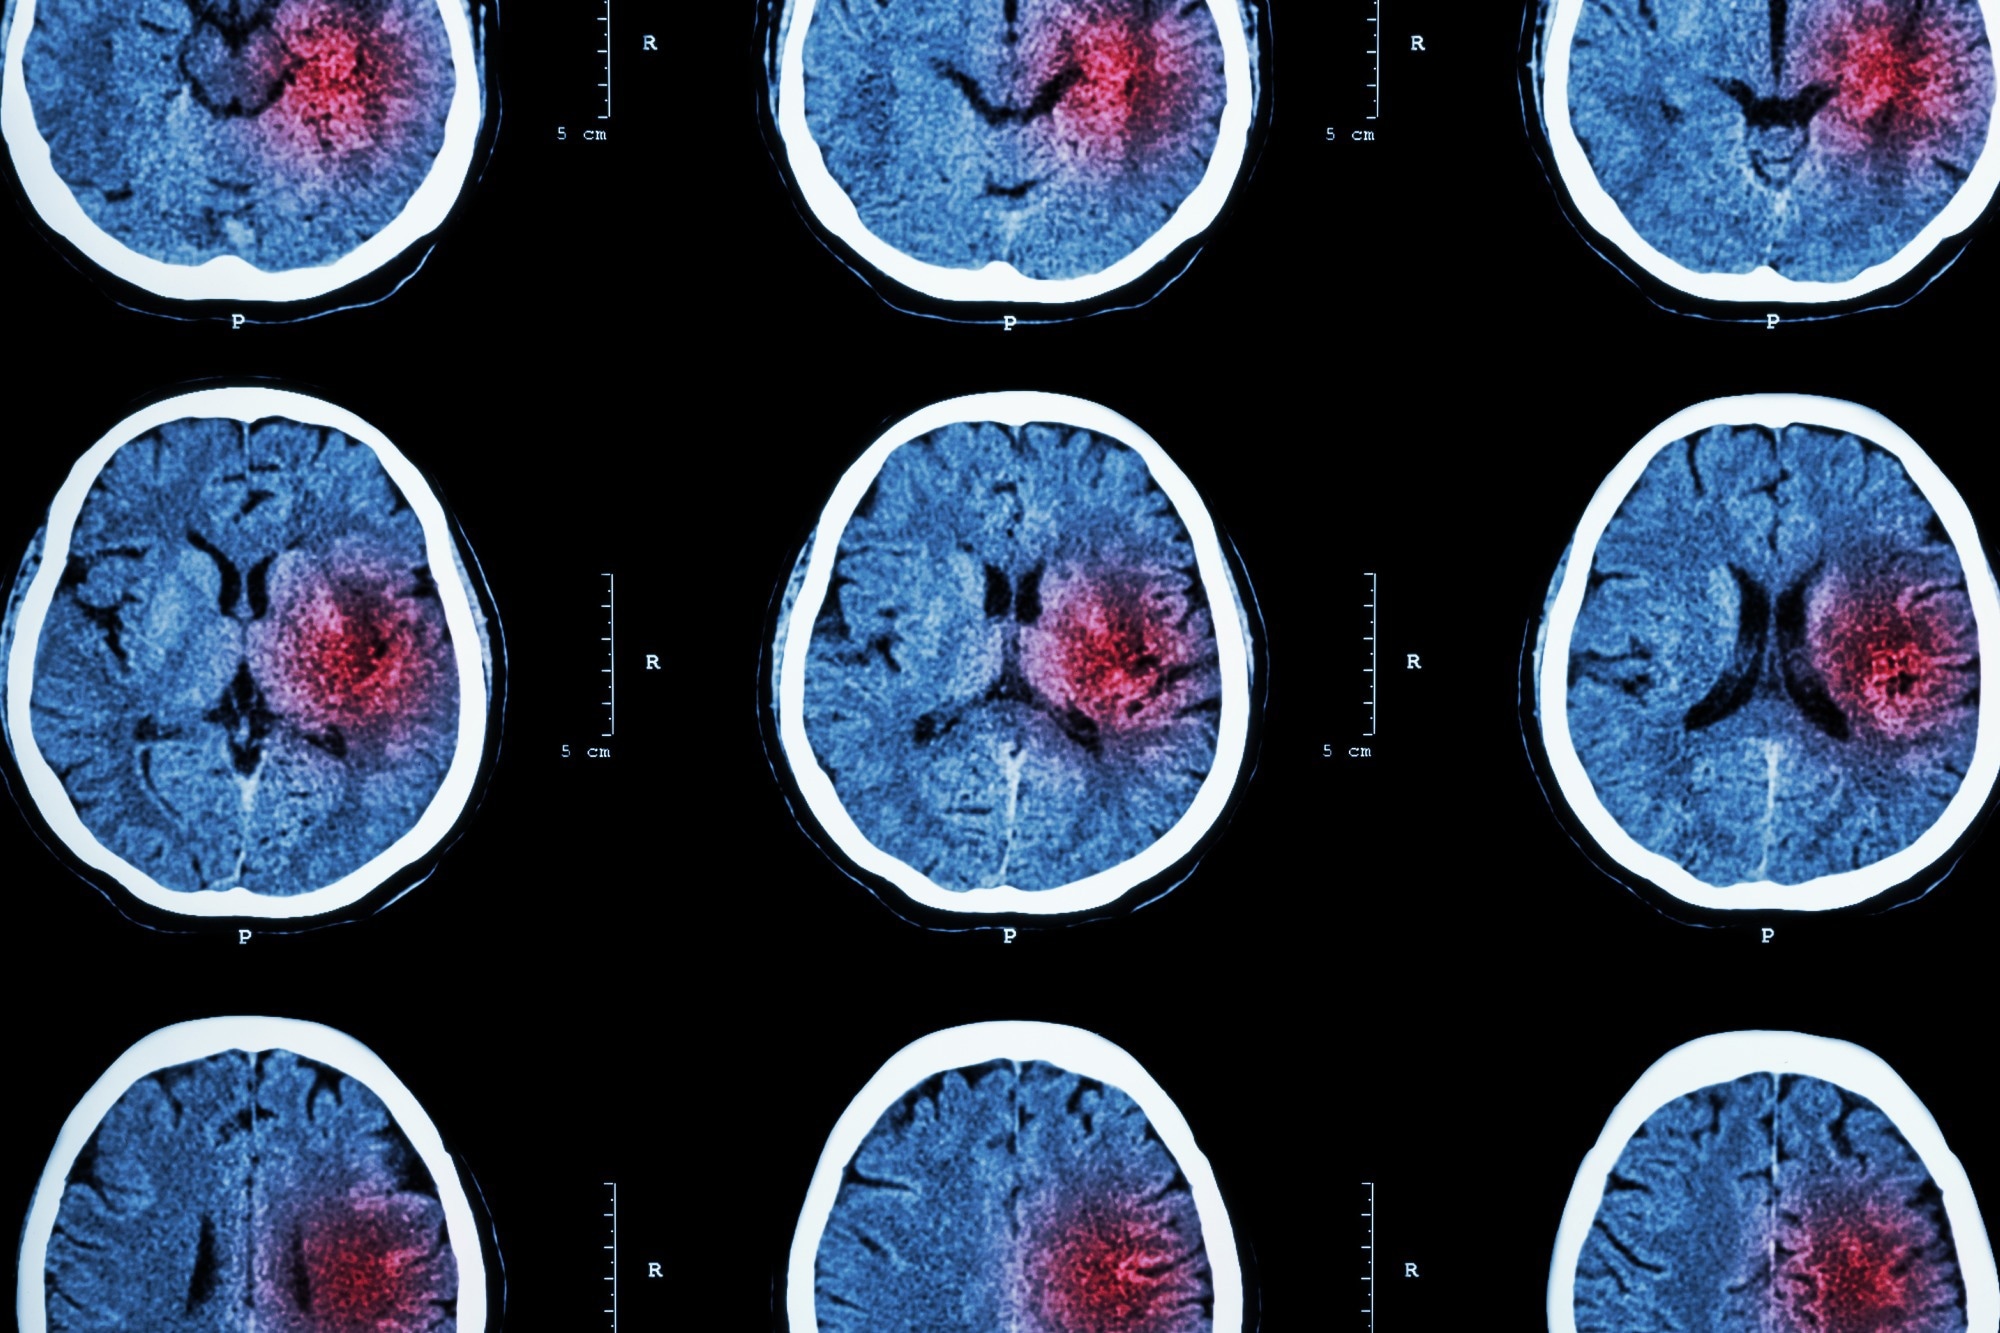

Schlaganfälle treten auf, wenn die Blutversorgung eines Teils des Gehirns unterbrochen wird. Können Sie uns mehr darüber erzählen, warum es zu einem Schlaganfall kommt und was mit den Gehirnzellen passiert, wenn ihre Blutversorgung unterbrochen wird?

Ein Schlaganfall tritt auf, wenn ein Blutgefäß, das Sauerstoff und Nährstoffe zum Gehirn transportiert, entweder durch ein Gerinnsel blockiert wird oder platzt. Daher gibt es zwei Arten von Schlaganfällen: ischämisch und hämorrhagisch.

Ischämische Schlaganfälle – die am häufigsten vorkommen und 87 % aller Fälle ausmachen – treten auf, wenn ein Blutgerinnsel zu einem Gefäß im Gehirn wandert und die Blutversorgung unterbricht. Dies verhindert, dass das Gehirngewebe Sauerstoff und Nährstoffe erhält, und Gehirnzellen können innerhalb von Minuten absterben.

Die andere Art von Schlaganfall, hämorrhagischer Schlaganfall, ist oft seltener als ischämischer Schlaganfall, kann aber schwerwiegender sein. Diese Arten von Schlaganfällen werden durch ein geplatztes Gehirnaneurysma oder einen Bruch geschwächter Blutgefäße verursacht.